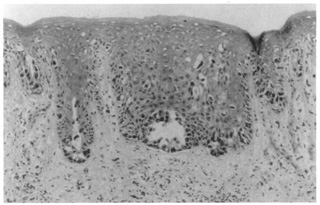

Pemphigus represents a group of diseases that has circulating antibodies directed against intercellular substances or keratinocyte surface antigens. A cleavage plane in the granular layer is characteristic of superficial pemphigus; a suprabasalar or midepidermal plane is characteristic of the most severe form, pemphigus vulgaris. Clinically, superficial, flaccid blisters rapidly erode and spread easily when compressed. Histologically, the keratinocytes separate immediately above the basal layer, extending to the midepidermis (pemphigus vulgaris) without spongiosis. Individual keratinocytes appear rounded with prominent nuclei. No intercellular bridges are visualized, and there is no significant inflammation in an early lesion (Fig. 10). A direct immunofluorescent study (skin biopsy) and an indirect immunofluorescent study (serum) show intracellular deposition of immunoglobulin G (IgG) and complement proteins throughout the epidermis. Pemphigus vulgaris, often fatal before the advent of steroid and immunosuppressant treatment, still is a very severe disease

Fig. 10. Pemphigus vulgaris showing acantholytic keratinocytes in a suprabasalar vesicle.